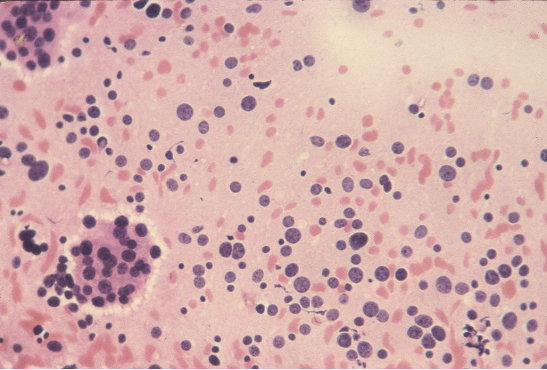

CYTOPATHOLOGY

Figs 1 and 2 from a mass in the right hypochondriac region.

Make your diagnosis.

Fig 1 : Giemsa x 100

Fig 2 : Giemsa x 400